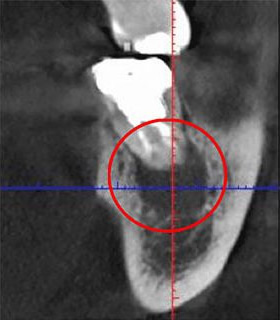

実際に「根管」の画像をご覧ください。歯の中にある黒い筋が根管です。

根管の形状は複雑で、狭いところは直径1mmもありません。こんな根管から、細菌に感染した組織を完全に取り除くのは、非常に難儀です。それにもかかわらず、日本国内の多くの歯科医院ではこの繊細な作業を「肉眼」で行っています。これも日本の根管治療の成功率が低い理由の一つと言えます。

当院では、根管治療の際には必ず歯科専用の顕微鏡「マイクロスコープ」を使用します。視野を数十倍にまで拡大することができ、緻密な手技が求められる根管治療においては欠かせない精密機器。

また状況に応じて「高倍率ルーペ」を併用しながら、拡大した視野の下で治療を徹底しています。

以下の画像は、マイクロスコープで見た患部の様子です。肉眼に比べてどれだけ精度の高い治療ができるか、お分かりいただけると思います。